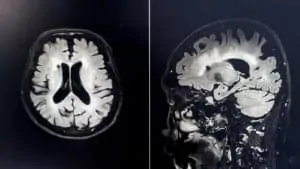

In a study published in the journal Nature Neuroscience, researchers from the University of Oxford used a specialized functional magnetic resonance imaging (fMRI) to study for changes in the brains of new jugglers. For the first time, the researchers were able to show changes in the brain’s white matter from a training intervention.

“We have demonstrated that there are changes in the white matter of the brain – the bundles of nerve fibers that connect different parts of the brain – as the result of learning an entirely new skill,” notes Dr. Heidi Johansen-Berg of the clinical neurology department at Oxford.

White matter differs from the more-well-known grey matter. The former is comprised of long nerve fiber clusters that conduct electrical signals across different brain regions. The latter is made up of the neuronal bodies responsible for the heavy computation and processing in the brain.